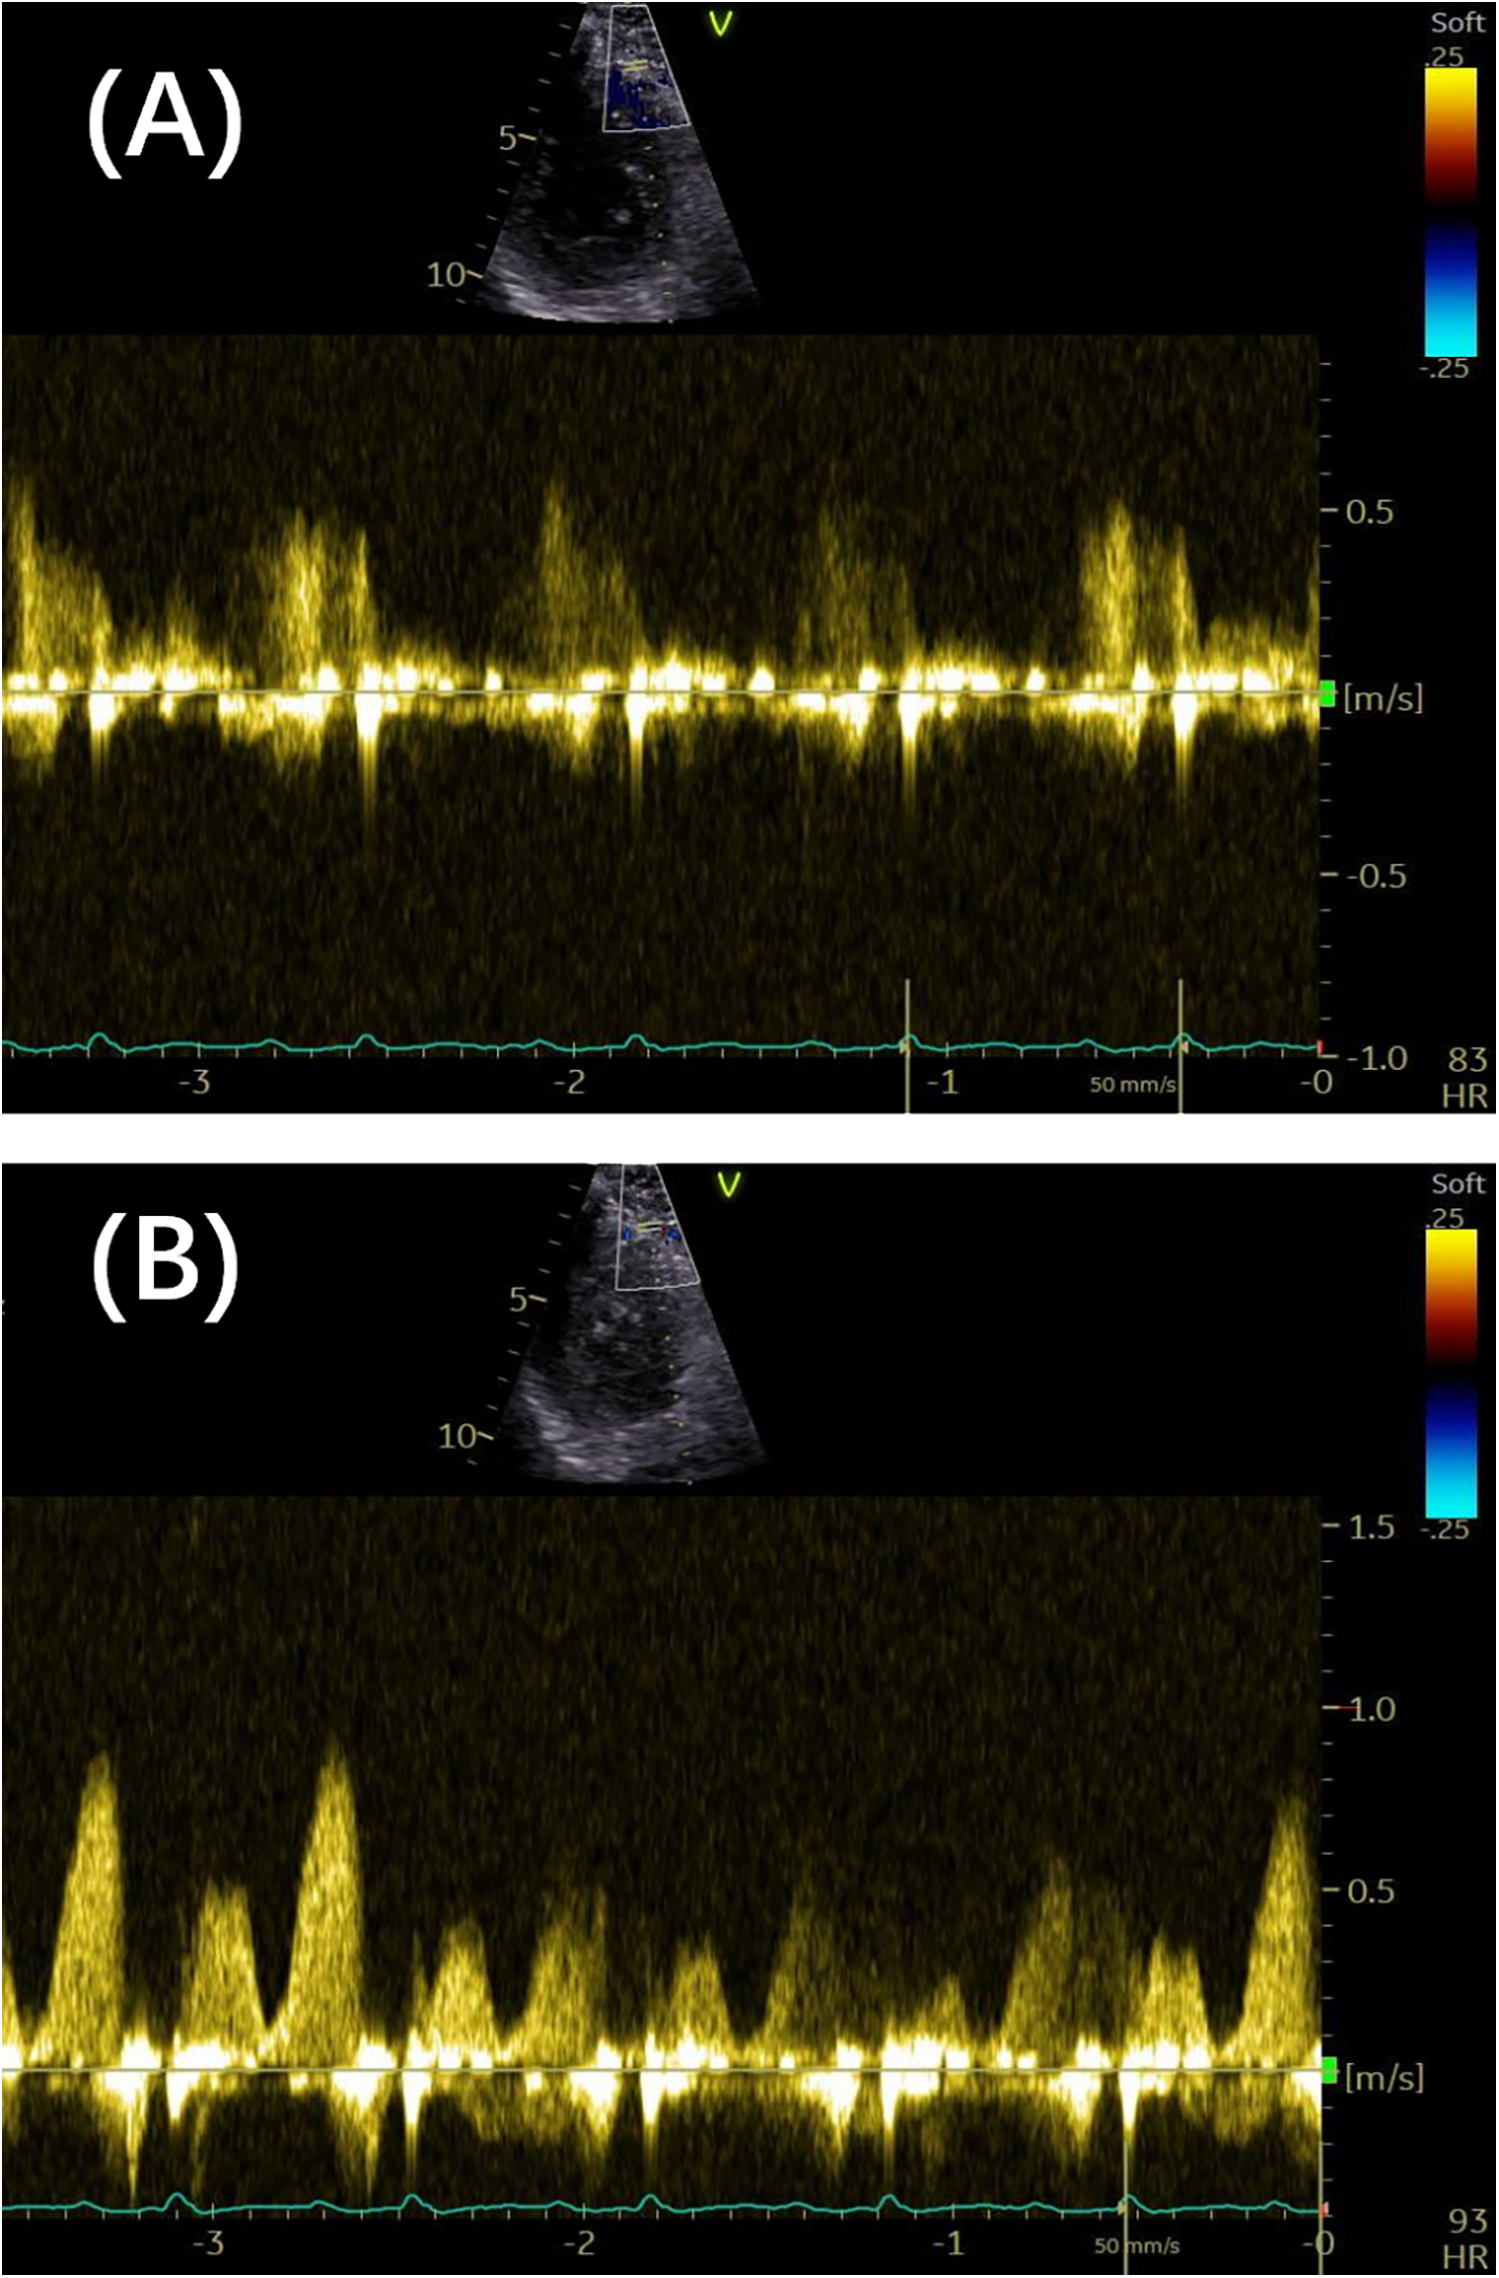

Peak flow velocity is defined as the highest instantaneous velocity within the systolic or diastolic phase, as measured from the coronary flow Doppler spectrum. The velocity is obtained by tracing the outer envelope of the Doppler signal using dedicated post-processing software, which automatically calculates the peak and mean velocities. The peak diastolic–systolic velocity ratio, peak stenotic to pre-stenotic diastolic velocity ratio, and pre-stenotic to stenotic mean diastolic flow velocity ratio are then calculated. The mosaic flow is regarded as a turbulent flow, characterized by locally persistent color aliasing due to rapid velocity exceeding the Nyquist limit. In detecting coronary stenosis, rescaling of the Nyquist limit of color flow Doppler at 0.48 m/s has been shown to be effective (15). Diastolic deceleration time (DDT) is measured from the peak diastolic velocity to the point where the initial decay slope line intersects with baseline. Diastolic pressure half-time (DPH) is the time interval required for peak diastolic velocity to decrease to of its initial value. Acceleration time (AT) refers to the time from the onset of flow to the peak velocity on the Doppler velocity curve. Systolic flow reversal (SFR) is a reversal of blood flow direction during ventricular systole, in the opposite direction to diastolic forward flow. Two unique coronary flow Doppler patterns have been identified as follows: the end-diastolic velocity sudden dip, which is caused by atrial contraction, is defined as a transient decrease in coronary flow velocity occurring between the P wave and the peak of the R wave on the electrocardiogram; and a unique square root sign is characterized by a steep velocity slope and followed by a plateau phase. Figure 2 illustrates representative parameters of these patterns.

Figure 2

(A) The outline of the Doppler spectrum was traced to calculate various parameters, including the peak velocity, mean velocity, and velocity–time integral. The white lines indicate the DDT and AT. The arrows show the presence of SFR (arrows). (B,C) Two Doppler spectrum features are indicated by the sudden dip in end-diastolic velocity (arrows) and the corresponding time point of the dip (dashed lines). The square root sign patterns are indicated by arrows. DDT, diastolic deceleration time; AT, acceleration time; SFR, systolic flow reversal.